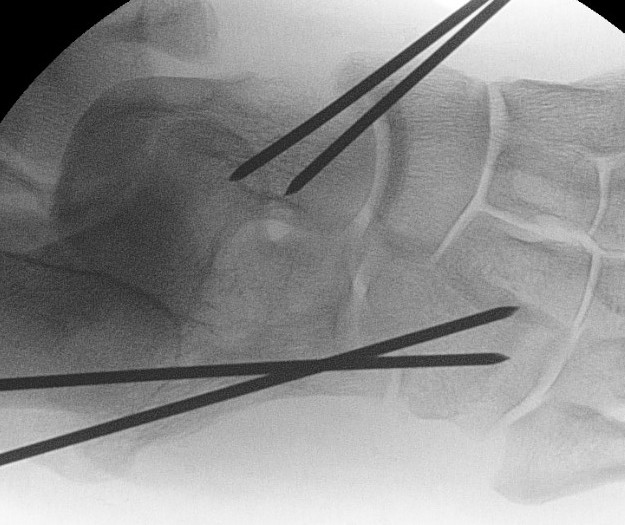

Pure ligamenous dislocation fixation

- percutaneous K wires

Urgent closed +/- reduction reduction

Anatomic reduction and stabilization